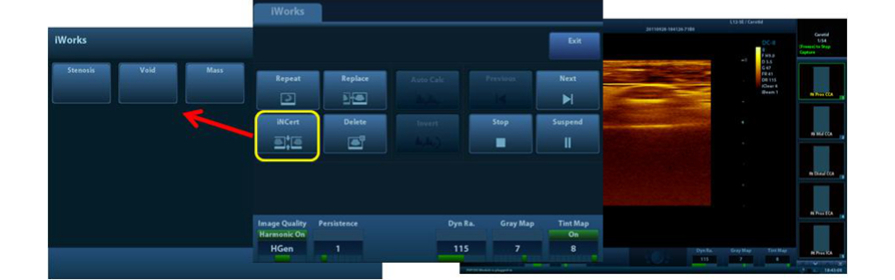

iWorks?

Una herramienta inteligente que le permite centrarse m├Īs en el paciente. Ayuda a reducir de forma significante el tiempo de escaneo del paciente mediante la estandarizaci├│n y la funci├│n definida por el usuario.